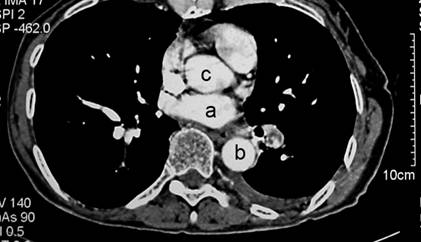

Préciser les structures

anatomiques identifiées par les lettres a, b, c.

Quel(s) est(sont) le(s) signe(s)

scannographique(s) en faveur de ce diagnostic sur le cliché ci-joint ?